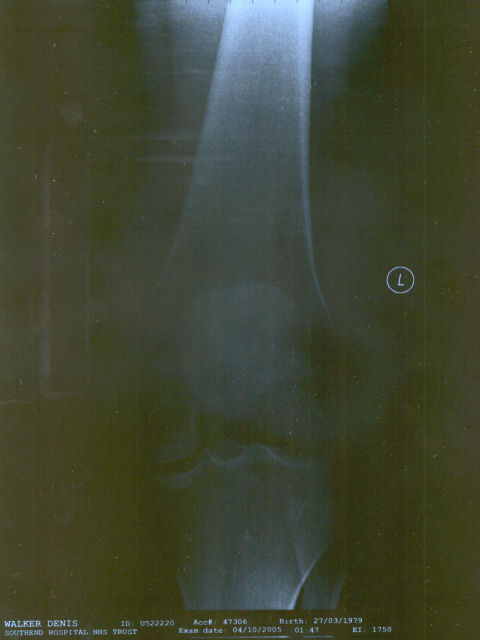

Some X-rays of my left knee...